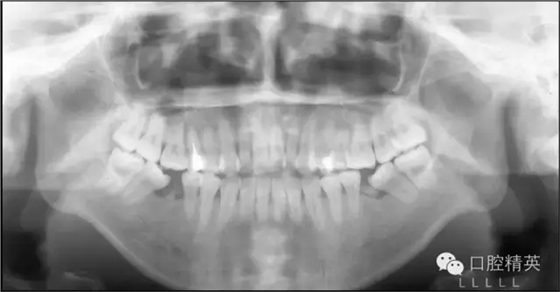

自上個(gè)世紀(jì)末開始至今,微螺釘種植體支抗在正畸領(lǐng)域的應(yīng)用已有近20年的歷史。而隨著其被越來越廣泛靈活地應(yīng)用于正畸臨床工作中,其在垂直向上的獨(dú)特優(yōu)勢(shì)也越來越突出,大致可以歸納為以下六個(gè)方面:高角病例全方位垂直向控制;改善露齦微笑——壓低上前牙;打開重度深覆合——壓低下前牙或同時(shí)壓低上前牙;矯正平面傾斜——壓低一側(cè)牙齒;壓低過萌長(zhǎng)磨牙——壓低磨牙;直立近中傾斜的磨牙——直立并壓低磨牙。本文將以結(jié)合典型病例的方式對(duì)以上六種微螺釘種植體支抗在垂直向上的應(yīng)用一一論述說明。

高角病例

全方位垂直向控制的概念

高角病例全方位垂直向控制的概念主要涵蓋了兩個(gè)方面,即針對(duì)磨牙的后部垂直向控制和針對(duì)上前牙的前部垂直向控制。

后部垂直向控制是基于高角骨面型的形成機(jī)制提出的。研究指出,高角骨面型的形成主要是由于相對(duì)較小的髁突垂直生長(zhǎng)量,和相對(duì)較大的上頜骨垂直生長(zhǎng)量及上下頜后牙牙槽突垂直生長(zhǎng)量,所共同導(dǎo)致的下頜骨后下旋轉(zhuǎn)所致。

簡(jiǎn)言之,即髁突與磨牙區(qū)的垂直生長(zhǎng)量失衡。對(duì)這類患者,即使是正處于生長(zhǎng)發(fā)育期者,我們也很難寄希望于其髁突的生長(zhǎng)在正畸治療中或治療后能自動(dòng)超過磨牙區(qū)的垂直生長(zhǎng),進(jìn)而控制住其下頜平面,因?yàn)橥ǔ;颊咴瓉淼腟N-MP角越大,下頜平面隨生長(zhǎng)發(fā)育會(huì)變得越陡。

因此,如果依賴髁突的自然生長(zhǎng),阻止其在正畸治療中因不可避免的磨牙升高而發(fā)生后下旋轉(zhuǎn)是很困難的,更不必說前上旋轉(zhuǎn)下頜平面。

既然我們很難改變患者髁突生長(zhǎng)不足的問題,就只好從控制其上頜骨及磨牙區(qū)的垂直生長(zhǎng)著手了,由于抑制生長(zhǎng)本非易事,控制患者的磨牙高度就成了控制其下頜平面最切實(shí)可行的手段。而通過壓低磨牙來控制高角患者的下頜平面,乃至實(shí)現(xiàn)其下頜平面的前上旋轉(zhuǎn)正是后部垂直向控制的概念及意義所在(圖1)。

圖1 通過壓低磨牙進(jìn)行后部垂直向控制

前部垂直向控制則是指控制上前牙向上向后移動(dòng)。 這一概念源于Tweed-Merrifield技術(shù)的方向性力系統(tǒng)。這一技術(shù)一直被認(rèn)為能夠?yàn)棰蝾惛呓腔颊邘碜罴训某C治效果,技術(shù)標(biāo)志之一就是著名的方向性力系統(tǒng),即通過控制患者的下后牙和上前牙來控制其下頜平面和合平面,實(shí)現(xiàn)這一控制的所有力的合力矢量均需向上向前,所需方向性力由牽引皮圈和可調(diào)整方向的J鉤頭帽提供。最終實(shí)現(xiàn)下切牙直立于基骨之上,上前牙向上向后移動(dòng),為下頜骨的前上旋轉(zhuǎn)創(chuàng)造條件,而這也正是前部垂直向控制的概念及意義所在(圖2)。

圖2 向上向前的方向性力系統(tǒng)

當(dāng)直絲弓矯治技術(shù)與微螺釘種植體支抗相結(jié)合,對(duì)高角病例進(jìn)行前后部全方位垂直向控制時(shí),其具體方法可簡(jiǎn)單歸納為表1所示的內(nèi)容。

表1 直絲弓矯治技術(shù)與微螺釘種植體支抗相結(jié)合,對(duì)高角病例進(jìn)行前后部全方位垂直向控制的具體方法

在這一全方位垂直向控制的理念中我們需要明確,后部垂直向控制,不論是磨牙的絕對(duì)壓低還是相對(duì)壓低(向遠(yuǎn)中直立或阻止其伸長(zhǎng))均是實(shí)現(xiàn)下頜平面前上旋轉(zhuǎn)的必要條件;而后上移動(dòng)上前牙的前部垂直向控制則是重要條件。關(guān)于這一點(diǎn)我們將在對(duì)四大類高角病例的典型案例所進(jìn)行的垂直向控制的分析中反復(fù)論述和強(qiáng)調(diào)。

四大類高角病例典型案例全方位垂直向控制分析

前牙開合 無露齦微笑

四大類高角病例為: 前牙開合,無露齦微笑; 前牙深覆合,無露齦微笑; 前牙深覆合,露齦微笑;前牙開合,露齦微笑。今天我們先來看一下,前牙開合,無露齦微笑高角病例的全方位垂直向控制。

Ⅰ類或Ⅱ類高角,前牙開合,但前牙垂直向唇齒關(guān)系正常,即沒有露齦微笑。這類高角病例將最直接而有效地發(fā)揮微螺釘種植體支抗在垂直向上的優(yōu)勢(shì)。在后部,應(yīng)用微螺釘進(jìn)行后部垂直向控制,壓低后牙,解除支點(diǎn),下頜平面前上旋轉(zhuǎn),前牙開合關(guān)閉。在前部,因?yàn)闆]有露齦微笑的問題,上前牙并不需要實(shí)現(xiàn)絕對(duì)壓低,僅需保持住其垂直向位置,阻止因上前牙的伸長(zhǎng)而導(dǎo)致下頜平面前上旋轉(zhuǎn)的空間減小。

因此,即使對(duì)于拔牙病例因鐘擺效應(yīng)上前牙有伸長(zhǎng)趨勢(shì),通過直絲弓矯治技術(shù)中的搖椅弓也能夠很好地實(shí)現(xiàn)前部的垂直向控制。這類高角患者的全方位垂直向控制充分說明,后部垂直向控制,即磨牙的絕對(duì)壓低或相對(duì)壓低(向遠(yuǎn)中直立或阻止其伸長(zhǎng))是實(shí)現(xiàn)下頜平面前上旋轉(zhuǎn)的必要條件,而后上移動(dòng)上前牙的前部垂直向控制并不是必需的,僅需控制即可,甚至上前牙稍有伸長(zhǎng),因?yàn)闆]有露齦微笑,只要下頜平面可以前上旋轉(zhuǎn)到一個(gè)理想的位置,頦部位置和形態(tài)得到顯著的改善,也是完全可以接受的。